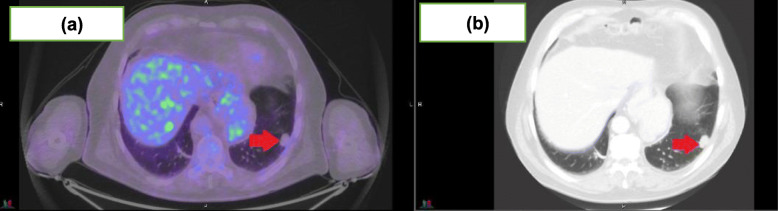

Using FDG-PET, 11 patients achieved a CMR (73% [95%CI:44.9, 92.2%]) of which only one achieved a complete response (CR) on RECIST1.1 assessment. Nine (82%) of these 11 patients had a partial response (PR) on RECIST1.1 for which two examples are shown in Figs. 1 and 2. Response assessments for FDG-PET and RECIST1.1 were concordant for the two patients with progressive disease. Table 2 highlights the imaging responses for this cohort. Cohen’s Kappa value for overall concordance between RECIST1.1 and PERCIST1.0 evaluation was − 0.18.

Fig. 1.

73 year old man with imaging for metastatic cutaneous squamous cell carcinoma to the lung post 12 months of cemiplimab 350 mg/3-weekly. a demonstrating a CMR to treatment and (b) demonstrating ongoing RECIST1.1 PR with measurable disease on CT